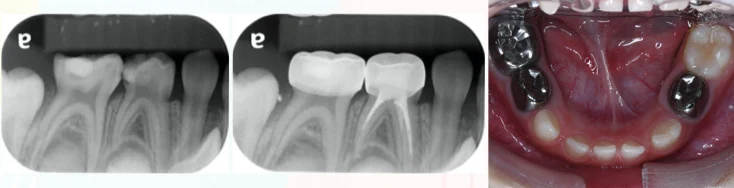

當蛀牙侵犯牙髓時,就必須把牙髓裡面的細菌及發炎的神經清理乾淨,防止細菌在往骨頭侵犯,進而影響恆牙的牙胚發展, 恆牙有獨立的牙髓系統,與乳牙根管治療互不影響! 蛀牙範圍過大或做過根管治療的乳牙,必須套上小鋼牙保護起來 防止崩裂以及降低再蛀牙、感染情況發生 在生長恆牙的同時並,不影響換牙喔!